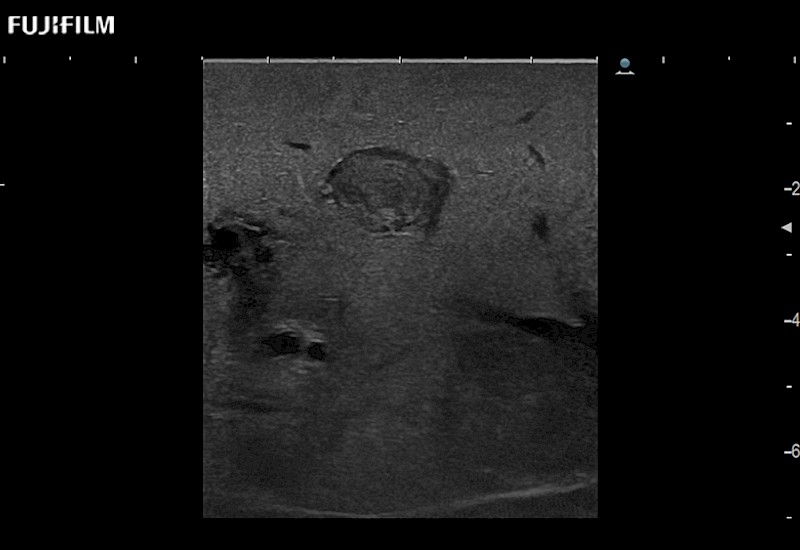

Exclusive linear array robotic surgery transducer.

Features: